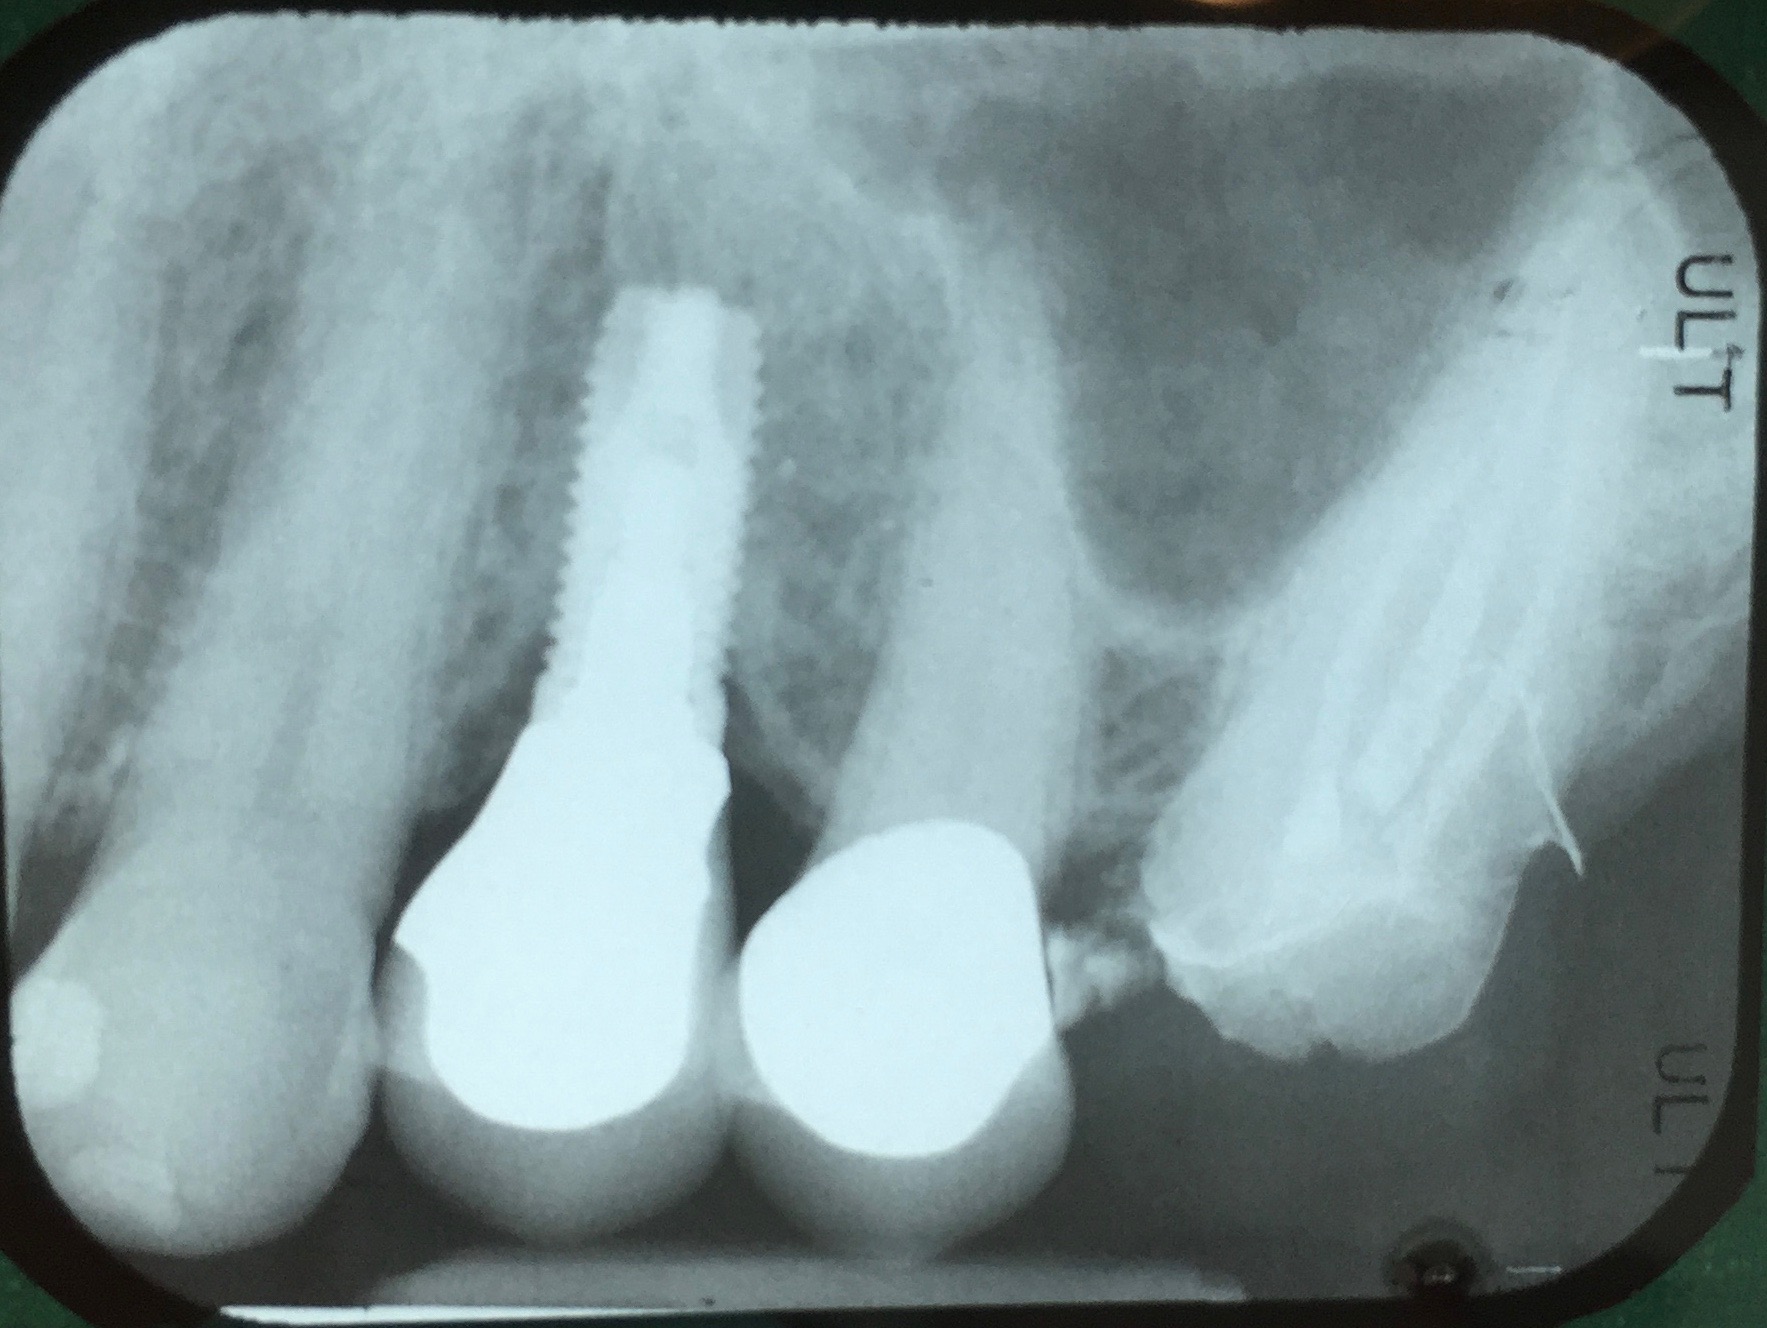

Fig 16. Radiograph depicting closed contact at time of implant insertion.

Figure 16

Fig 17. Open proximal contact between implant and adjacent tooth 3 years post insertion.

Figure 17

Open Proximal Contacts

During the initial planning phase for implant therapy, the dental practitioner should not assume that the existing position of the teeth within the dental alveolus will remain stationary throughout the patient’s lifetime. Long-term follow-up of implant restorations has proven that often it does not remain stationary, regardless of the age of the patient. Open contacts have frequently been reported between implants and adjacent teeth.30

Open proximal contacts between implants and adjacent teeth have been attributed to ongoing craniofacial growth31 and vector forces mesializing tooth position (Figure 16 and Figure 17).32 These changes, particularly in the esthetic zone, can contribute to differences in incisal edge position, gingival margin height, and the facial contour and alignment of the dental arch (Figure 18 and Figure 19).31 Jemt et al30 studied a population of 28 consecutive anterior implant crowns followed for 15 years. During this time, only 8 patients demonstrated no movement of the adjacent teeth; 55% of adjacent teeth displayed palatal tooth movement, predominately in the female population.30 Shifting of teeth can contribute to occlusal changes leading to uneven occlusal load and distribution among the arch.31 Similar to adjacent open contacts between teeth, any open contact can lead to food impaction/accumulation, pocketing, and inflammation of the interdental tissue.